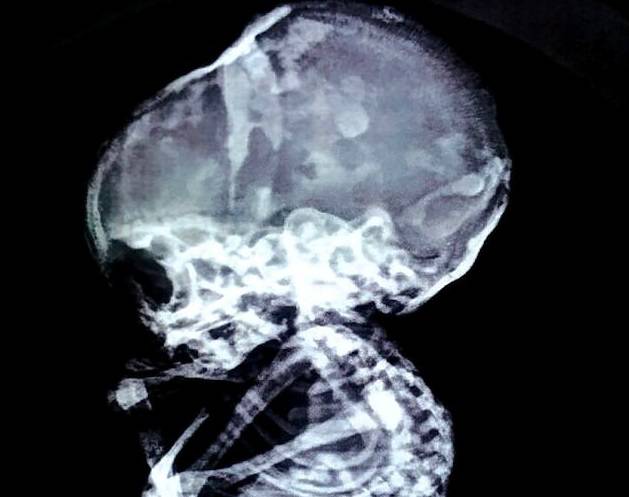

Cancro: le cure innovative al Bambin Gesù

Un nuovo gruppo di lavoro sta sperimentando l'immunoterapia che potrebbe aiutare i pazienti affetti da tumore a curare la malattia.